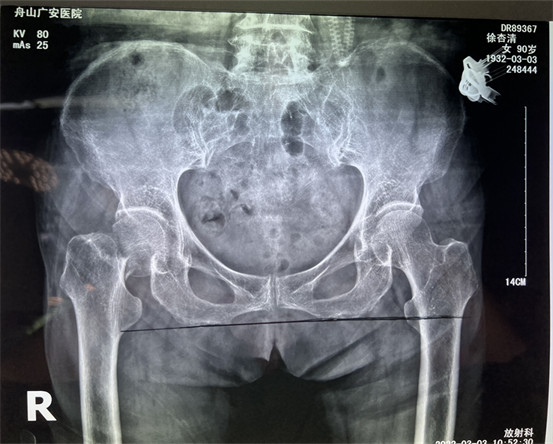

幾周之前,90歲高齡的老太太行走時(shí)不慎摔倒,發(fā)生股骨頸骨折,合并心臟病等多種內(nèi)科疾病。股骨頸骨折的危害極大,常發(fā)生于七十、八十歲嚴(yán)重骨質(zhì)疏松的老年人,如果不能給以合適的手術(shù)治療患者會(huì)喪失行走能力,同時(shí)臥床時(shí)間長(zhǎng)會(huì)才出現(xiàn)許多并發(fā)癥,危及生命。

在舟山廣安醫(yī)院辦理住院后,經(jīng)過白黎明副主任和骨科中心羅軍主任的系統(tǒng)檢查和全面評(píng)估后,決定為患者做了微創(chuàng)智能DAA人工髖關(guān)節(jié)置換。